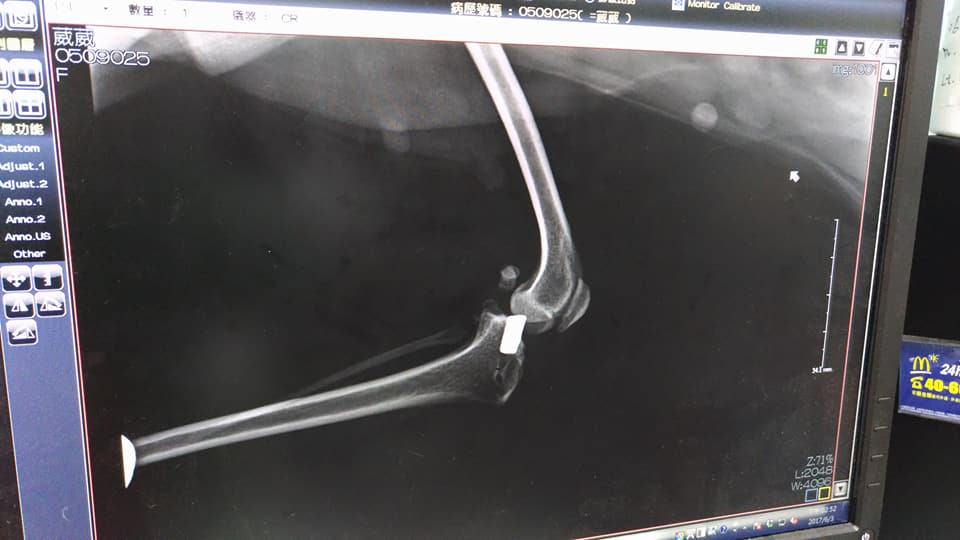

今日葳葳照X光,看術後膝蓋骨的復原狀況,X光片顯示,復原狀況還不錯,膝蓋骨有長在正確的地方。

8/19 沐恩 葳葳開刀出院

葳葳右腳手術結束,復健方式同左腳,一日三次

8/25 沐恩 葳葳回診拆線

右腳傷口復原良好,但他不敢用右腳,所以要加強復健,早晚各一次,時間允許下午一次